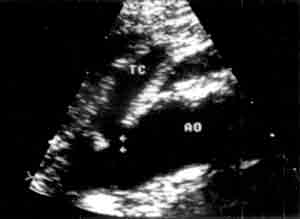

Рис. 5. УЗ-изображение атеросклеротической бляшки в устье чревного ствола.

ТС - чревный ствол

АО - аорта.